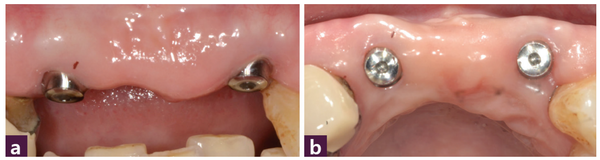

그러나 위 환자의 경우는 치은퇴축이 돼 있어서 연조직의 수직 재생을 도모하기 위해 순측의 marginal gingiva에 맞춰 Magic Post 2mm를 모두 노출시켜 식립했고 이것이 본 증례의 가장 핵심이 되는 치료 방법이다 [그림 7].

위 환자 처럼 Gingival recession이 돼 있는 경우 에서 환자의 현재 순측 marginal gingiva에 맞춰 임플란트를 식립한다면 최종 보철물의 치 관 길이가 매우 길어져 심미적으로 좋지 않은 결과를 가져올 수 있다.

그래서 MagiCore의 Magic Post margin을 순측의 marginal gingiva에 맞춰 Magic Post 2mm 모두 노출 또는 Magic Cuff를 1mm 정도 노출시킴으로써 그 공간에 연조직이 재생될 수 있는 환경을 만들어 주고 발치 전 치아의 두께보다 가는 Magic Cuff를 구개측에 위치시킨다면 순측의 발치 전 thin gingival biotype이 thick gingival biotype으로 개선되면서 보철 후 치은의 on-growth 현상을 기대할 수 있다. [그림 6, 7, 8, 9]

식립 1개월 후 연조직의 양호한 치유 상태와 순측의 풍부한 연조직 sealing을 관찰할 수 있다. 치조제와 치은연의 보존 및 개선도 관찰된다 [그림 10].